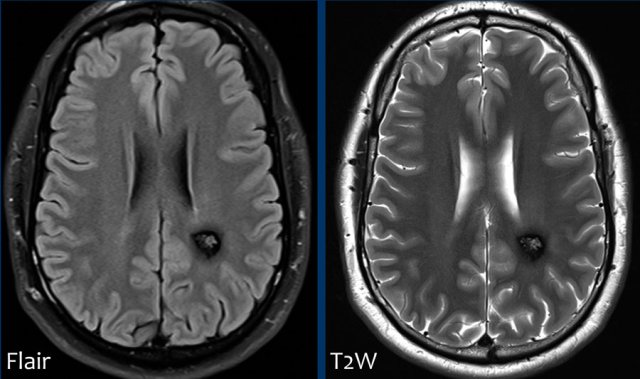

FLAIR-image shows the following findings:

• Subcortical leuko-ariosis (yellow arrow)

• Subtle FLAIR hyperintense signal in the subarachnoidal space of the central sulcus left hemisphere, this can be compatible with blood (white arrow).

FLAIR is an excellent sequence to detect SAH in the subacute phase with almost a sensitivity of 100% from day 4-14.

T2W-image confirms the presence of an abnormality in the central sulcus with low signal intensity corresponding to hemoglobin breakdown products.

Susceptibility weighted imaging confirmed the SAH and also reveales multiple small punctate lobar hemorraghes, leading to the diagnosis of cerebral amyloid angiopathie (CAA).